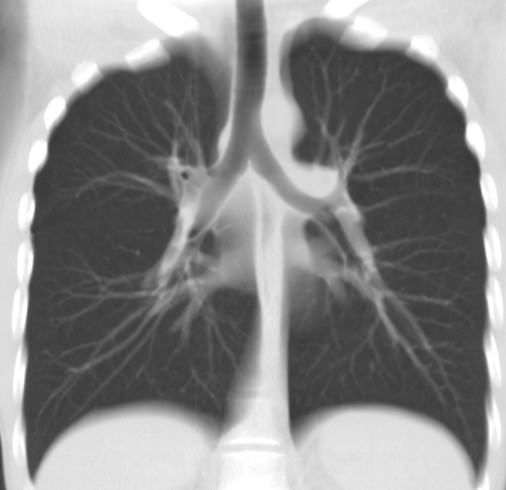

Органы дыхания

КТ легкихПоскольку КТ намного лучше других методик показывает состояние полых, наполненных воздухом или жидкостью структур, процедура очень эффективна при выявлении патологий органов дыхания (легких, трахеи, бронхов), а также окружающих тканей (сосудов, лимфоузлов). На снимках отображается полная картина пневмонии, что позволяет оценить степень поражения легочной ткани, локализацию патологических очагов.

Хорошо определяет КТ признаки легочной гипертензии (на снимках выявляется расширение легочной артерии с одновременным ослаблением сосудистого рисунка), новообразования различной природы, инфекционные и неинфекционные (например, астма) заболевания, абсцессы, плевриты, жидкость в плевральной полости, эмфизему и другие патологии.